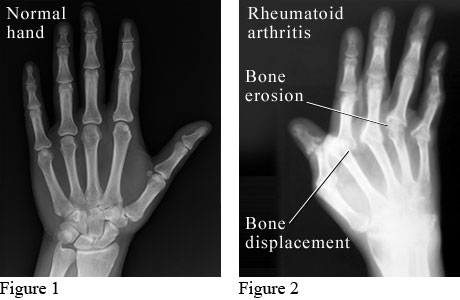

X-ray images showing a normal hand and a hand with rheumatoid arthritis

The X-ray on the left shows a normal hand.

The X-ray on the right shows a hand with advanced rheumatoid arthritis. "Bone erosion" means cartilage and bone are worn away. "Bone displacement" means that a bone has moved out of its normal position. This X-ray shows how bone erosion and bone displacement can change the shape of the hand.